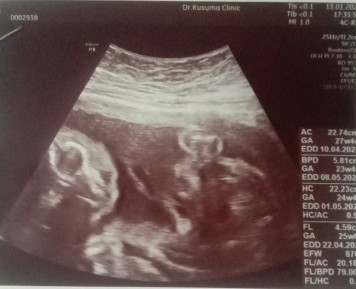

22w2dยังไม่รู้เพศเลยค่ะ